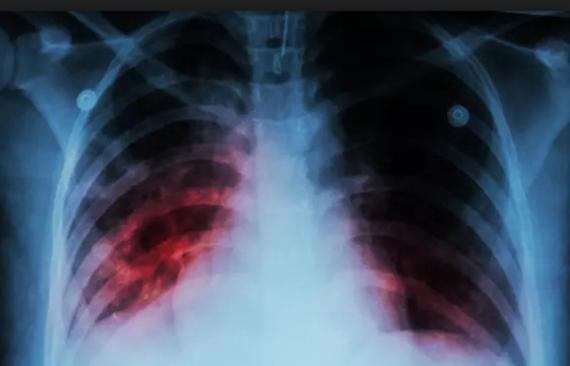

Tuberculosis, enfermedad silenciosa, pero de cuidado

En un año se reportan entre 450 a 500 casos en el Tolima.

La tuberculosis es causada por la bacteria Mycobacterium Tuberculosis, es una enfermedad infecciosa que suele afectar a los pulmones y se presenta en el Departamento con mucha frecuencia.

Según el boletín epidemiológico de la semana 10 del 2022, en el Tolima se han notificado 92 casos en los que se encuentran 78 de tuberculosis pulmonar y 14 de tuberculosis extrapulmonar.